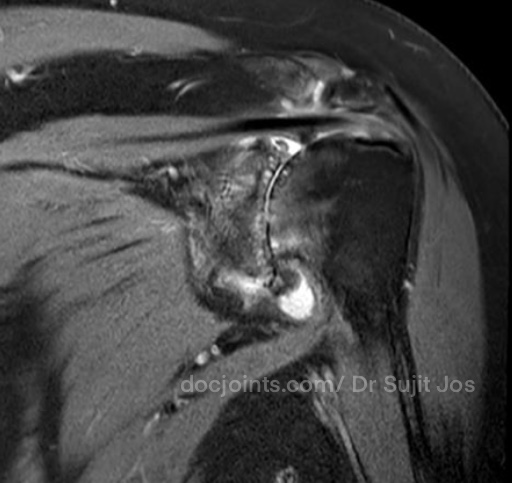

On presentation to the OP, the lifting power of the shoulder was significantly affected on strength testing (emply can test indicating supraspinatus tendon tear) and outward rotation was very weak (indicating Infraspinatus tendon tear). Xray and MRI images attached below.

There was significant fatty infiltration of the rotator cuff muscles along with osteoarthritis of the shoulder joint. Treatment options were discussed. Reverse shoulder arthroplasty is the modern treatment for this type of pathology, which can restore muscle function by orienting the shoulder centre of rotation in such a way that the Deltoid muscle can help in elevating the limb from neutral position (Read more about Reverse shoulder replacement >>).